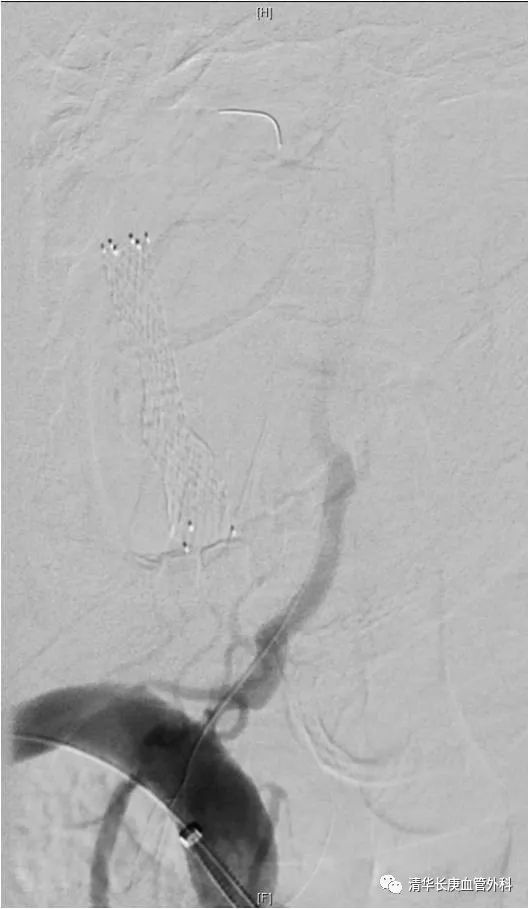

下肢动脉粥样硬化闭塞症、糖尿病足腔内治疗往往充满悬念,完全闭塞严重钙化病变的“遭遇战”极具挑战。张童副主任医师为大家演示了膝上、膝下不同部位的CTO病变突击战,风格迥异:一例胫前动脉CTO病变,通过胫后动脉Loop技术重建足背动脉,在此基础上“接力”逆穿足背末节趾间动脉起始段,方案应变坚决果断,思路出乎意料,入路精准稳定,博得满堂彩。

膝上动脉病例是一例股浅动脉粥样硬化闭塞,亮点一是通过病变的导丝导管技术秉承真腔通过理念,时长30秒!亮点二是目前备受关注的定向减容技术,操作行云流水,斑块悉数就擒。亮点三是药涂球囊扩张成形,无需支架置入,体内不留异物,延长通畅时间。